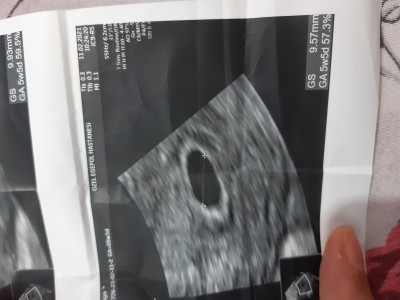

Arkadaşlar ben anlamadım hangisi dogru ultrasonda 5+3 yaziyo altta 5+5 yaziyo hangi dogru kac haftalik oldugumuzu hangisi dogru gosteriyo bu arada suan 6 haftaligim ama 6 hafta kac gunluk oldugumu anlayamadim

Bi en altta sagda 5w5d diye yaziyo bide ustte solda 5w3d diye yaziyo

Canim 5+5 olan doğru ben öyle biliyorum

Usg ye göre hesap yapma. Usg o haftalik gelişime göre ölçüm yapiyor. Esas hafta son adet tarihinin ilk gününe göre hesaplanıyor ve dogum da bunun üzerinden hesaplanıyor.